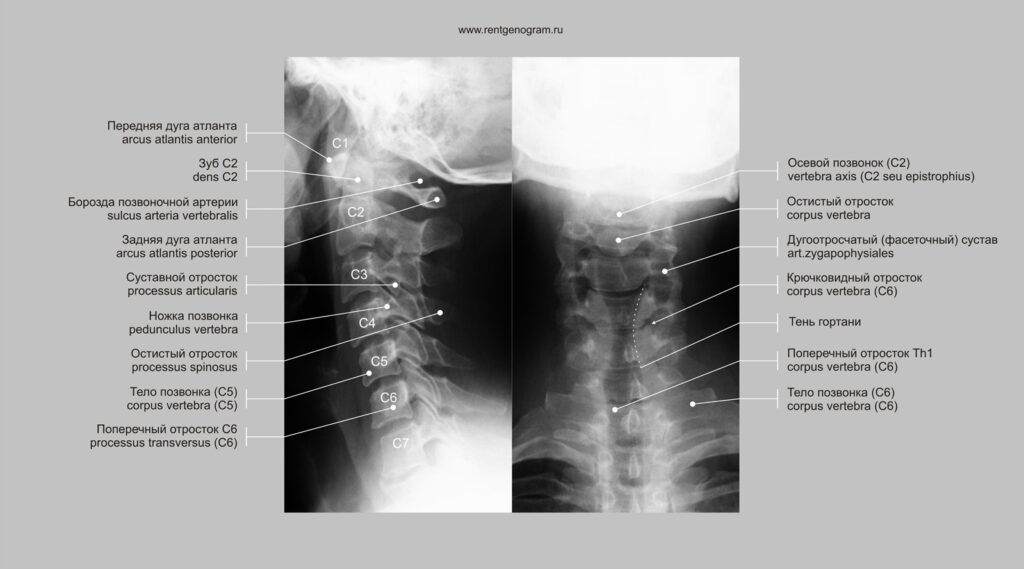

Фото 36 — Рентген позвоночника в профиле